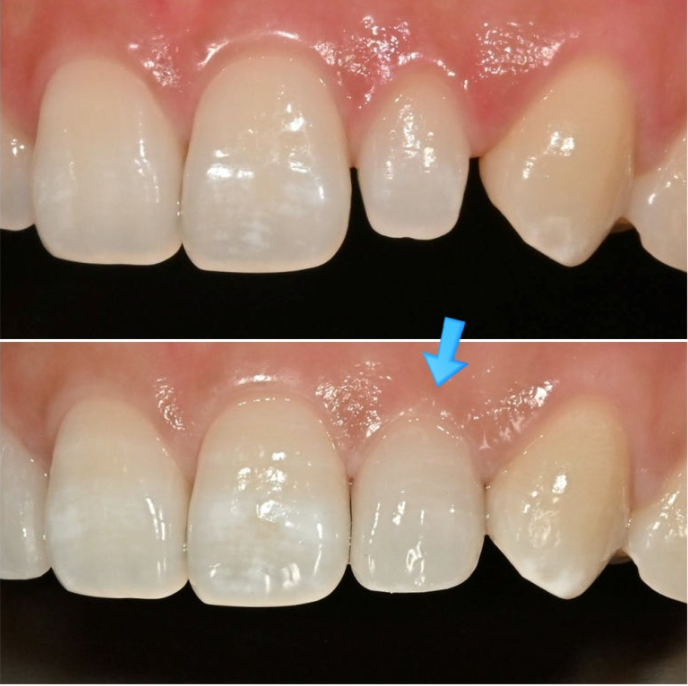

다만 앞니 전반에 퍼져있는 흰색 얼룩, 즉 반점치가 있는 상태입니다.

이정도의 얕고 넓은 반점치는 아이콘 치료로 치아를 갈지 않고도 치료가 가능하기에 아이콘을 먼저 권해드렸지만

왜소치에 각각 무삭제라미네이트 시술 후 모습입니다.

극강의 얇은 두께로 인해 본래 치아색이 우러나와 생기는 우윳빛 투명감은 젤라미의 특징입니다

표면의 아주 옅은 반점치 무늬가 보이시나요?

주변 치아와 질감 뿐 아니라 표면의 미세 무늬까지 구현하여 이질감을 없애 자연스럽게 어우러지도록 합니다.